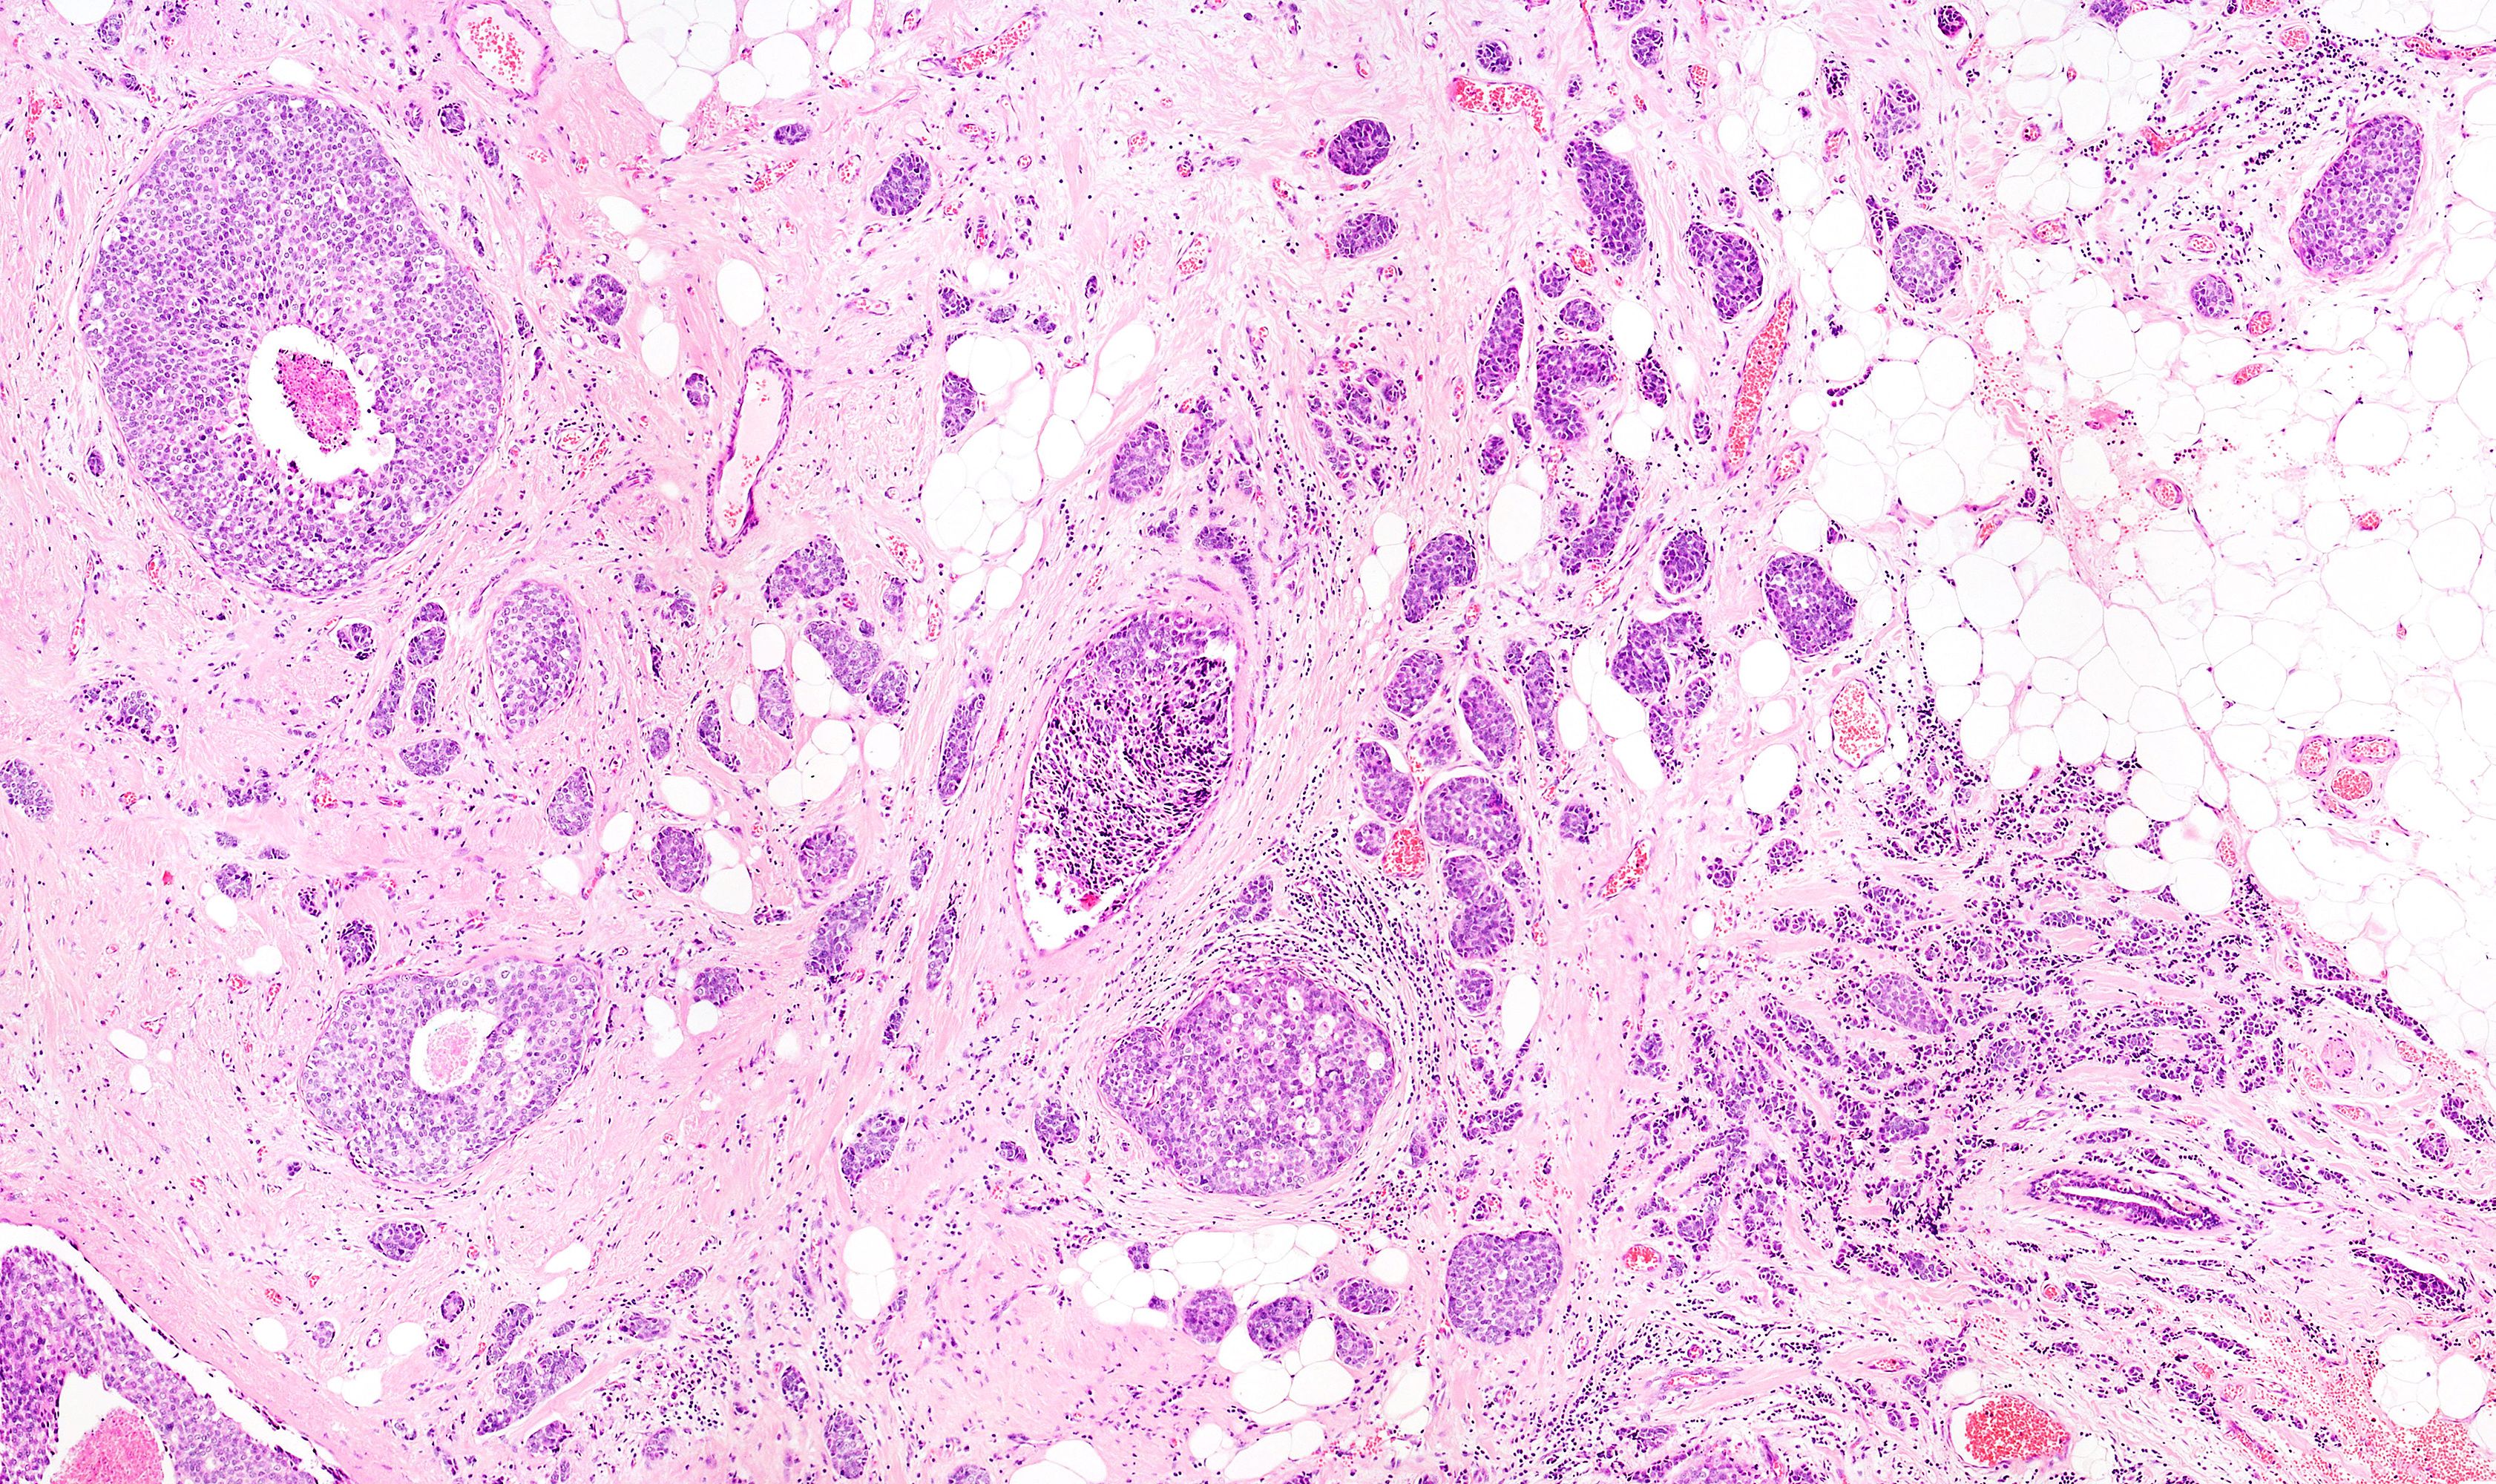

The success of dose-dense therapy led Dr. Norton to speculate about the molecular nature of tumors and whether the Gompertzian model applies. And here is where Dr. Norton throws in some gardening. He believes that a breast with cancer doesn't look like a complete and organized organ. It appears more like a bed of weeds rather than the oak tree, and each clump of weeds is a small and independent seed, or tumor.

This, he says, explains why the tissue laden with malignant tumor is much more dense than normal. It is anything but an organized mass, but rather a collection of small clumps of dense cell growth that together make up the tumor and account for its density. Further, he speculates, each tumor cell clump follows the initial rapid growth of the Gompertzian model, explaining the rapid growth of the tumor as a whole.

But how do these collections of small tumor clumps arise in the first place? In this model, cancer is a disease of self-seeding, and the tumor gives rise to its own weed clumps through self-metastases.